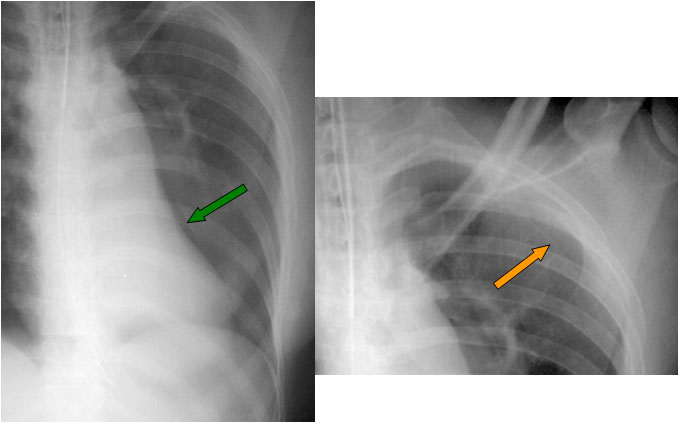

Signo de neumotórax en la radiografía anteroposterior, en decúbito supino. Un pequeño neumotórax de localización anterior puede pasar desapercibido; cuando el neumotórax perfila el surco costofrénico anterior da lugar a una imagen de doble diafragma (flechas verdes) que nos debe hacer sospechar la presencia del neumotórax.

En este caso también puede verse la línea pleural (flechas amarillas) por la extensión lateral del neumotórax. En otros pacientes, el signo del doble diafragma puede ser el único signo de neumotórax.

Este signo tiene un valor limitado, ya que las lobulaciones diafragmáticas pueden verse como doble diafragma.

Otro ejemplo, en un adulto. La flecha verde indica la banda medial mientras que la flecha naranja señala el neumotórax en posición lateral.